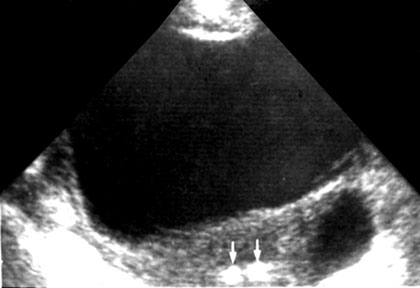

Acoustic Shadowing

An acoustic shadowing appears as a zone of reduced echogenicity (hypoechoic or anechoic black) and formed behind a strongly reflecting structure such as calcium containing bone.

Thus the visualization of soft tissue structures in the upper abdomen is obscured by overlying ribs, and those of lower pelvis by pubic symphysis.

This effect can however be exploited to reveal calcific gallstones, renal stones and atherosclerotic plaques (Figs 1.28A and B).

Similar shadowing can be caused by air in the lung or intestinal tract. Evaluating structures behind air containing bowel loop is often precluded by acoustic shadowing.

Figs 1.28A and B: (A) CBD calculus—a grossly dilated CBD (measuring 23 mm) is seen with a echogenic focus with shadowing at its distal end, (B) Shadows from overlying gases hindering visualization of posterior structures